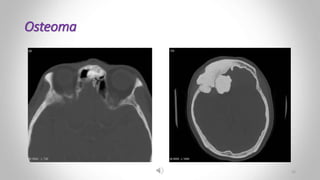

Osteoma :

• Is a benign tumor

• Consisting of dense bone

• They may occur in the paranasal sinuses.

 Osteoma:

• A well-defined area of dense cortical bone is present below the right acetabulum.

Osteoma